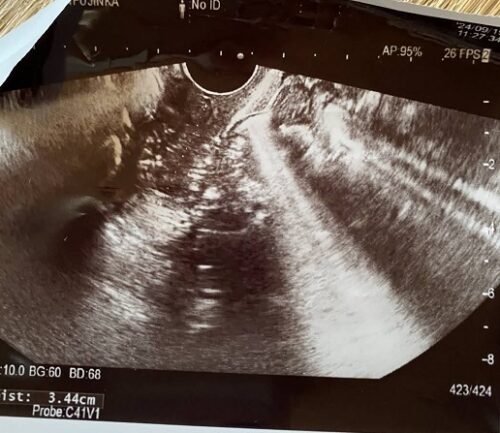

2025年のエコー